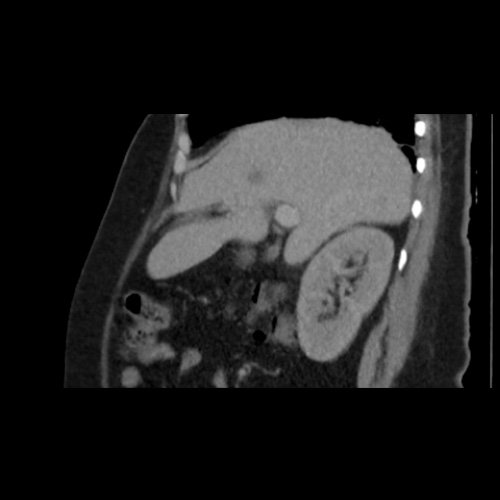

TC de abdomen y pelvis con contraste endovenoso (12/02/2026) Corte coronal: hígado de forma, tamaño y situación habituales, con superficie lisa y bordes agudos. Imagen hipovascular aislada de 15 mm en segmento V de aspecto inespecífico.

TC de abdomen y pelvis con contraste endovenoso (12/02/2026) Corte sagital: hígado de forma, tamaño y situación habituales, con superficie lisa y bordes agudos. Imagen hipovascular aislada de 15 mm en segmento V de aspecto inespecífico.

Tomografía de abdomen y pelvis sin contraste oral con contraste EV (12/02/26): El hígado es de forma, tamaño y situación habituales. Su superficie es lisa, y sus bordes son agudos. Imagen hipovascular aislada de 15 mm en segmento V de aspecto inespecífico. Sugiero complementar con RMI. La vía biliar intra y extrahepática es de calibre conservado. La vesícula biliar es de forma, tamaño y situación normales, sin imágenes que sugieran la presencia de litiasis. Tener en cuenta que este método puede pasar por alto litiasis colesterínicas. El bazo es de forma, tamaño y situación normales. El páncreas es de características normales. El conducto de Wirsung es de calibre conservado. Adenoma adrenal izquierdo de 16 mm. Ambos riñones son de forma, tamaño y situación habituales. Concentran y eliminan adecuadamente la sustancia de contraste. Sin evidencia de alteraciones calicopiélicas ni ureterales. La aorta, las arterias ilíacas primitivas, internas, externas y femorales, son de calibre y trayecto conservado, permeables. La vena cava inferior y las venas ilíacas primitivas, internas, externas y femorales son de calibre y trayectoria conservados, permeables. No se observan adenomegalias intraperitoneales, retroperitoneales, ilíacas ni inguinales. No se observan alteraciones a nivel del tracto gastrointestinal. La vejiga es de paredes lisas, sin presentar efectos de masa endoluminales ni parietales. Utero en AVF, lateralizado a izquierda. Pequeña hernia umbilical de contenido graso y escaso líquido intrasacro. No se identifican alteraciones en las estructuras óseas visualizadas.